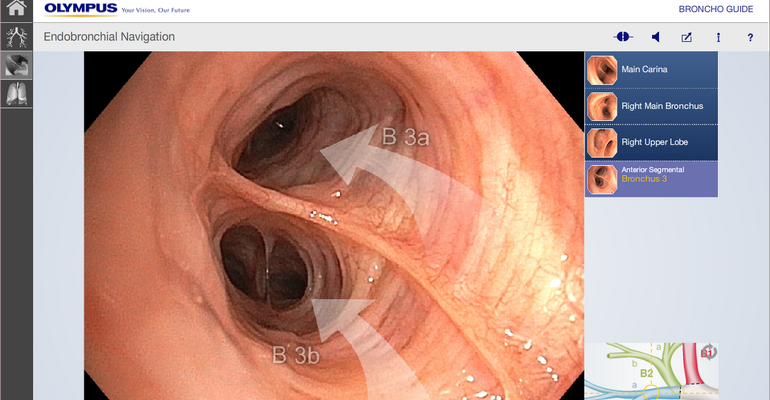

Вы выполняете, приближенное к реальности, обследование бронхиального дерева в HDTV качестве бронхоскопом BF-H190.

Реализована функция внутрипросветной эндонавигации по бронхиальному дереву!

Вы сможете последовательно начиная от карины, используя тачскрин, выбирать направление и изучать\вспоминать анатомию бронхиального дерев

Комментарии диктора статичных изображений и переходные видео применены для максимального облегчения пространственной ориентации и подробного объяснения о ангуляции и движении бронхоскопа во время исследования.ВИДЕО работы приложения можно посмотреть на сайте разработчика:

You are welcome to experience a bronchoscopic examination, almost as if it were done in a real clinical setting. Starting at the main carina, this app enables you to steer a HDTV bronchoscope through the bronchial tree step-by-step, from one carina to the next. Audio commentated still images and transitional videos are displayed facilitating spatial orientation and providing detailed explanation about the angulation and movement of the bronchoscope. Highly experienced medical experts have been involved in the development of this training app; however, please keep the following aspects in mind: